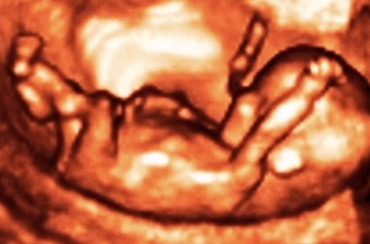

In cursul saptamaniilor 14 - 15 este foarte posibil sa percepi pentru prima data miscarile copilului tau. Unele femei percep miscarea copilului ca un tremur usor, delicat...

Hainele largi sunt absolut necesare pentru ca talia ta s-a modificat, iar burtica este din ce in ce mai evidenta. In plus, bebe nu trebuie sa se simta incorsetat.